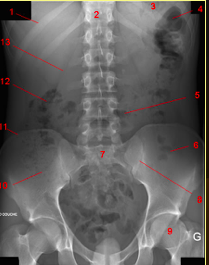

What does the following show?

Label A-D

Post-operative ileus

A: massive gastric distention

B: distended small bowel loops

C: air in colon & mild dilatation of sigmoid colon

D: Haustral fold in apex of sigmoid colon